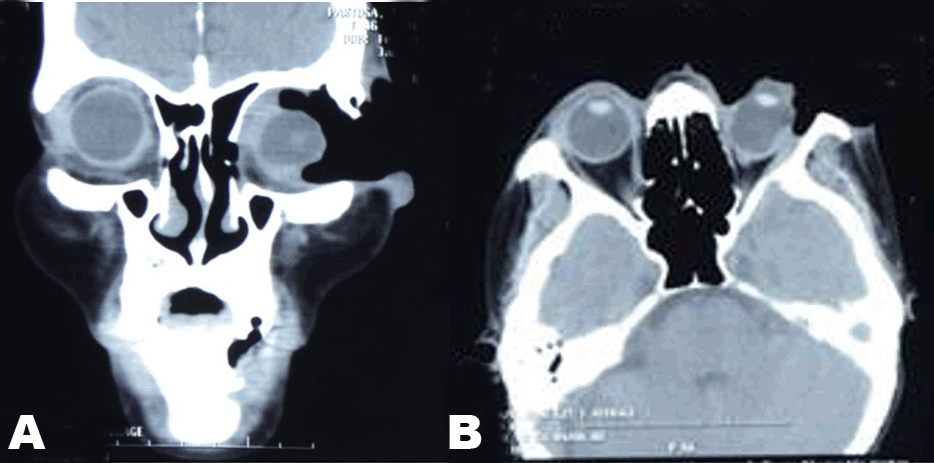

An assessment of Gorlin-Goltz syndrome was considered in this patient and further work-up was done. Orbital CT scan showed as seen in Figures 3 soft tissue mass invading the left orbit and deforming the left globe and a calcified falx cerebri. Transvaginal ultrasound was done revealing normal results. Chest radiograph showed in Figure 4 showed no bifid ribs.

Figure 3:(A and B) (Left) Coronal, and (Right) Axial CT scan showing invasion of the left orbit, deformed left globe and a calcified falx cerebri.